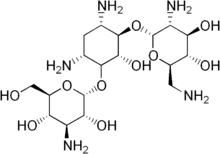

| Formula | C18H37N5O10 |

Bekanamycin (INN; kanamycin B) is an aminoglycoside antibiotic.[1][2]